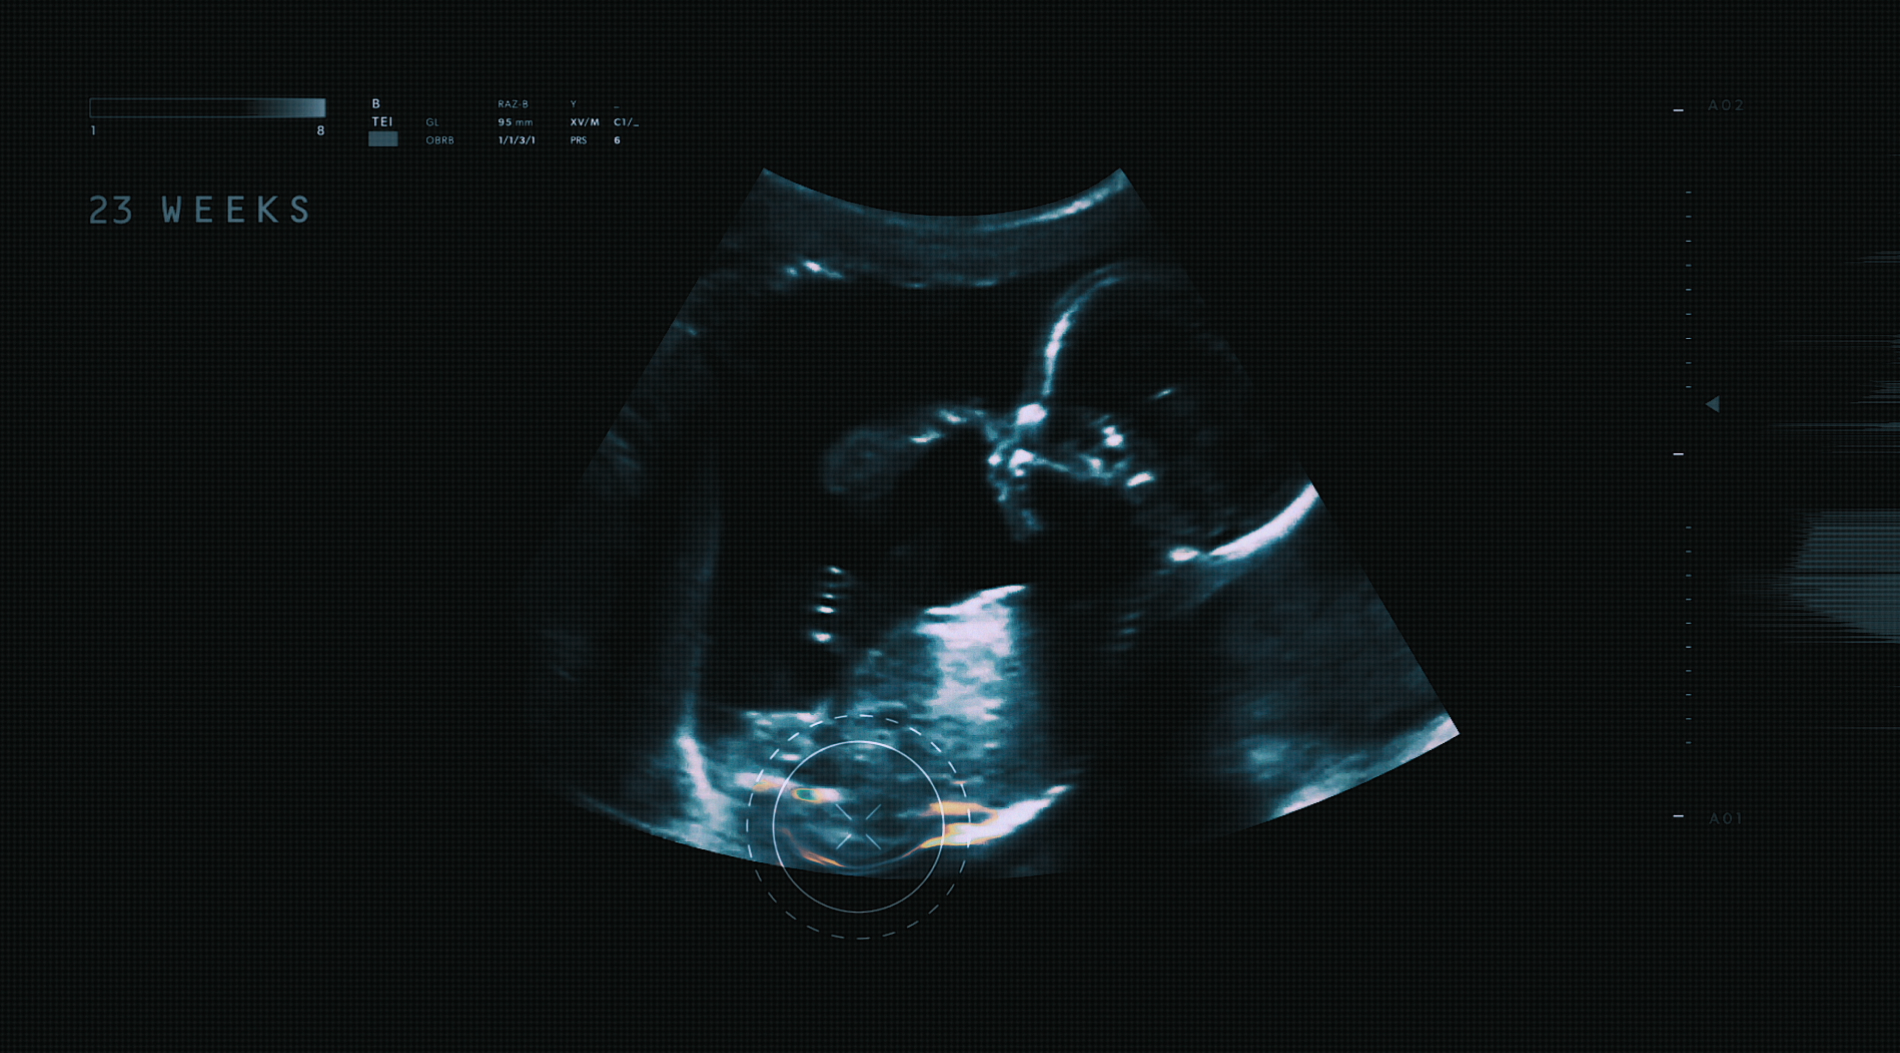

Children’s Hospital Colorado is a top 10 pediatric hospital in the USA. Born Twice is one of many powerful stories that demonstrates Children's expertise and innovation and gives weight to their long standing strapline “Here, it’s different”.

We just needed to tell it simply. We chose the juxtaposition of an ultrasound and snippets of conversation between the parent and doctor. We called on Ben Lukas Boysen to recreate the classic lullaby Twinkle Twinkle and there we have it; a miraculous story of a baby born twice.